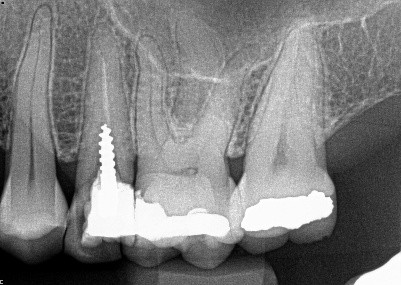

2. (Select ONE OR MORE correct answers)

Which of the following may complicate the extraction of tooth 4.7?